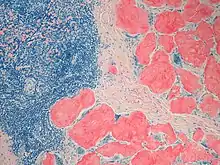

Cardiac amyloidosis. H&E stain.

Micrograph showing amyloid deposition (red fluffy material) in the heart (cardiac amyloidosis). Congo red stain.